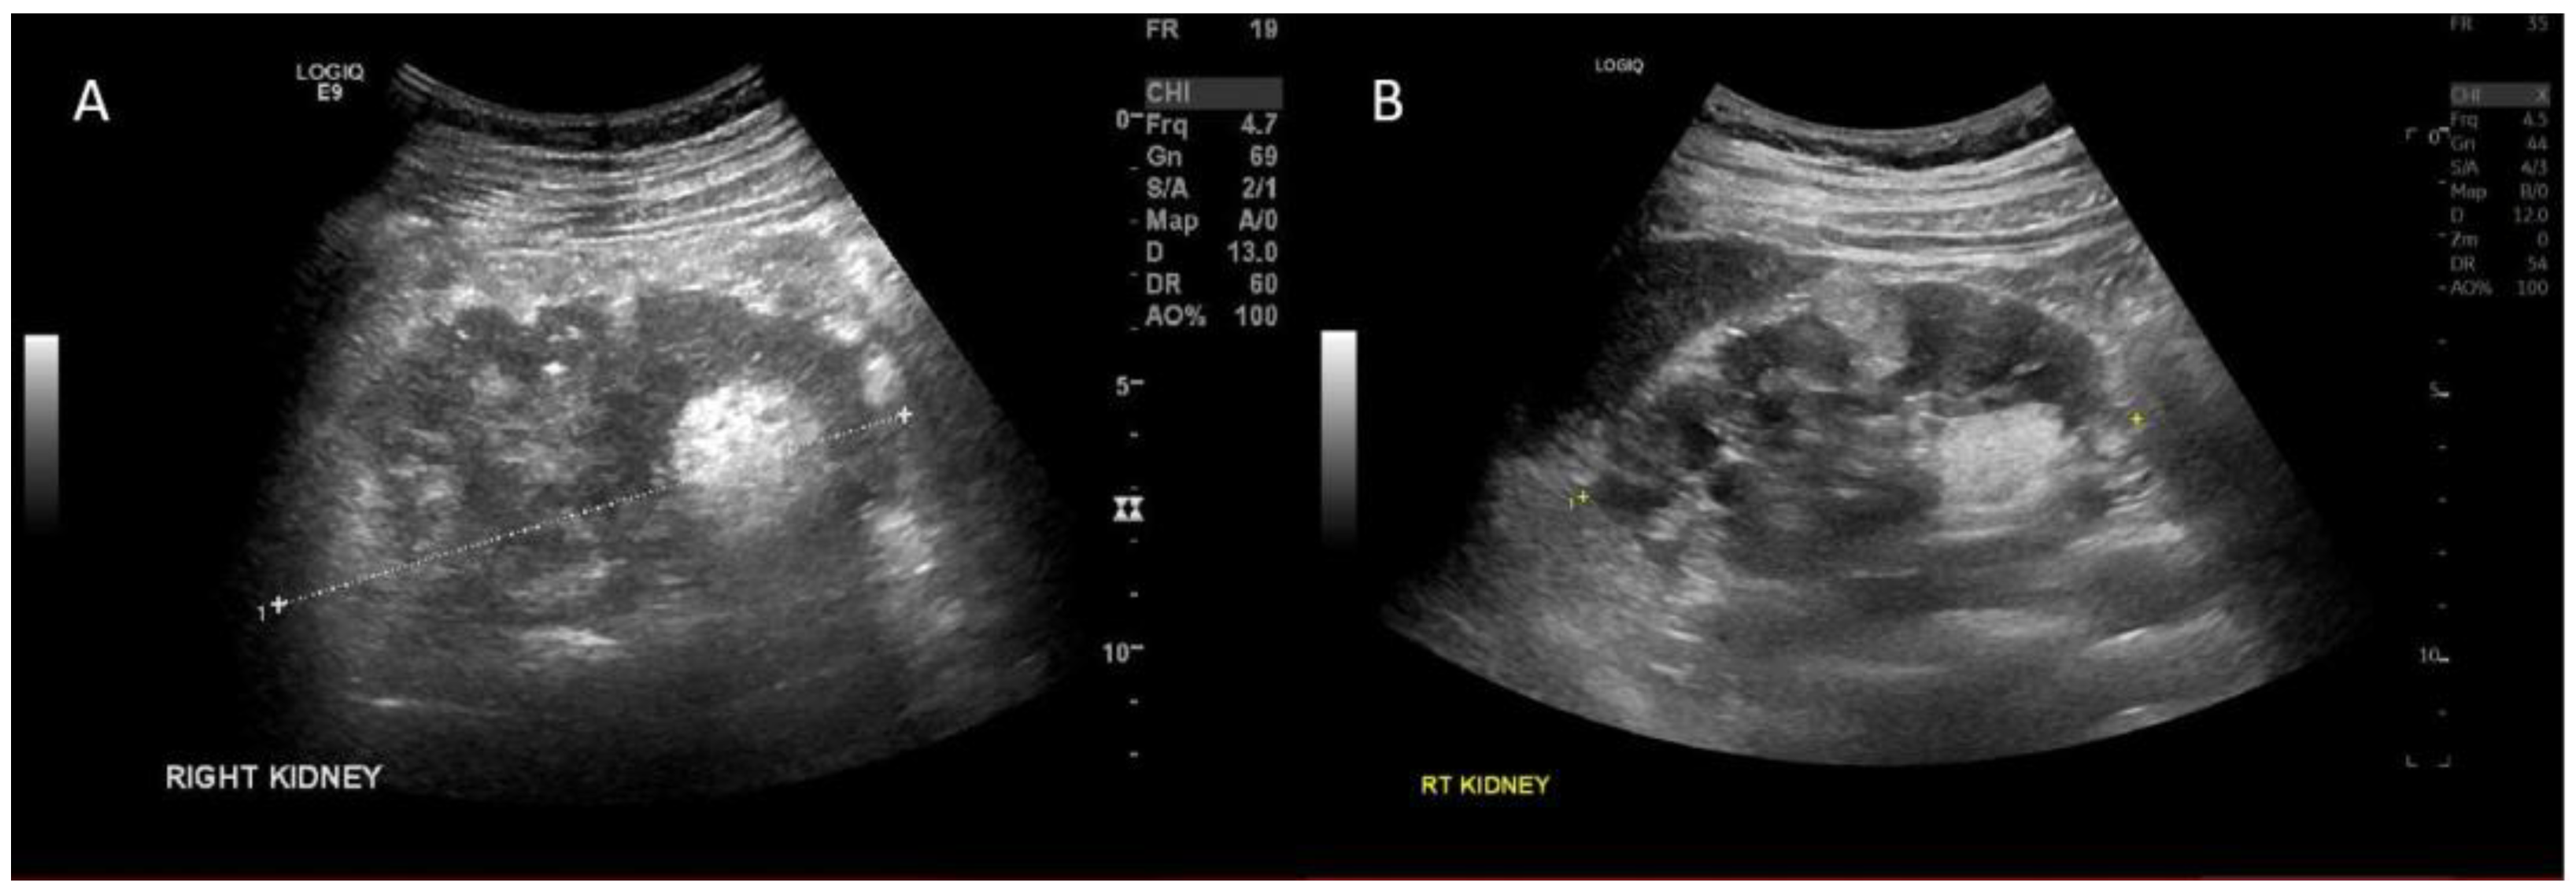

2. Case Report